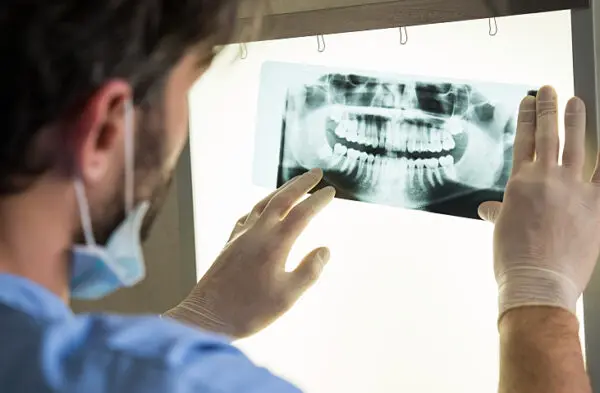

5. X-Rays

Your dentist takes X-rays of your teeth to look for structural deficiencies, conducts checks of your gums and tongue for indicators of disease, and examines the state of your enamel for wear and vulnerabilities. If you’re consistently skipping a dentist appointment, you could be at an increased risk of tooth decay, bad breath, gum disease, infection, or even cancer. X-rays are sometimes done at dental checkup appointments to ensure that the teeth haven’t shifted or moved over time.